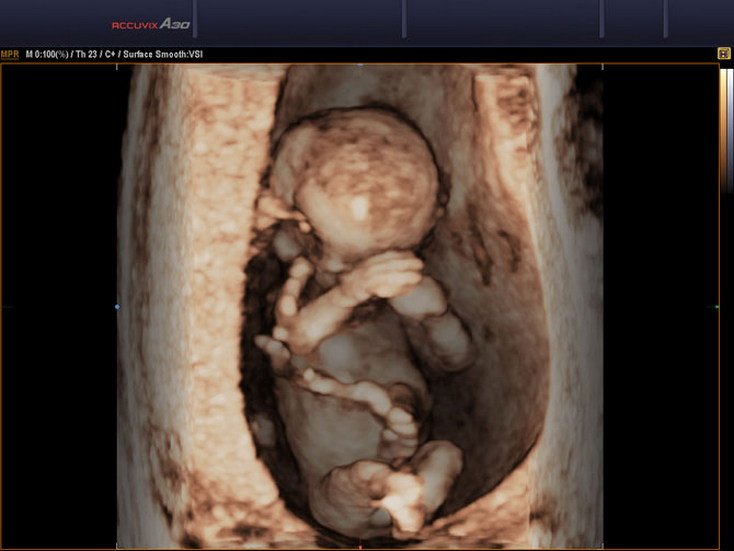

4D Snography-Early Pregnancy